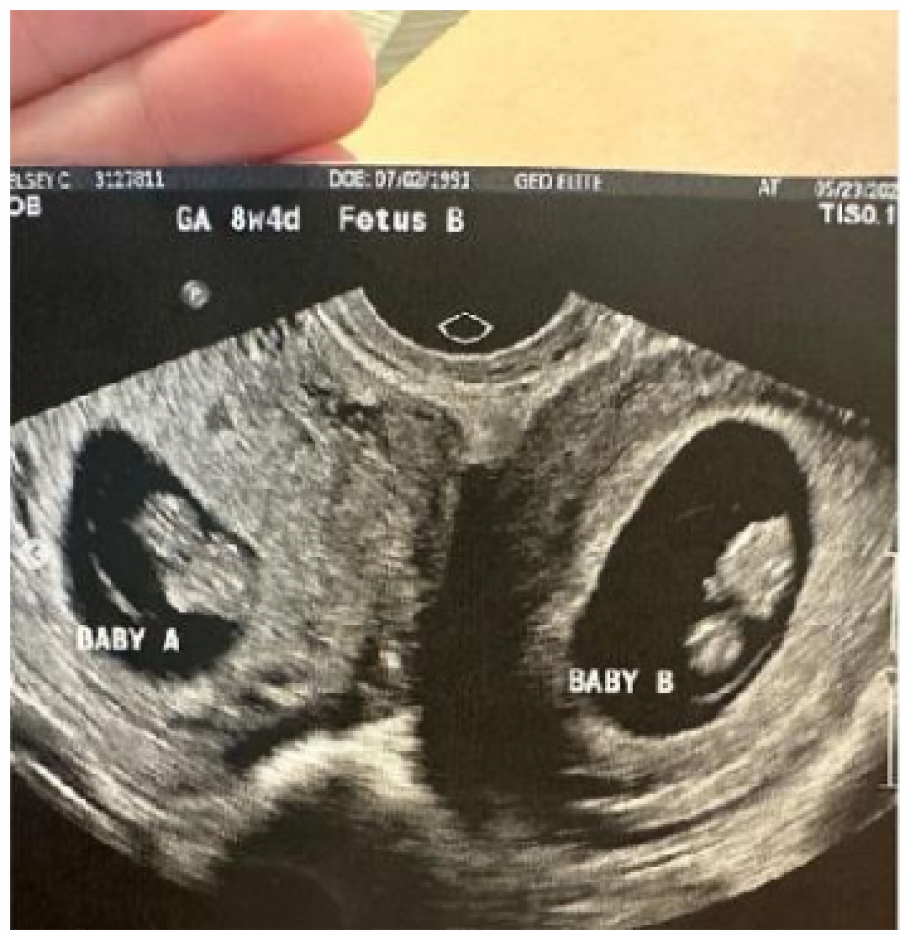

Tokom rutinskog ultrazvučnog pregleda u maju, majka troje dece saznala je da će roditi dvoje dece, ali da su fetusi prisutni u obe materice.

„Nismo mogli da verujemo. Tokom prvog ultrazvuka smo se mnogo smejali“, napisala je na Instagramu.

Trudnoća u obe materice je neverovatno retka. Hačerovoj je rečeno da su šanse jedan u 50 miliona, a poslednji poznati slučaj desio se u Bangladešu 2019. godine kada je dvadesetogodišnja Arifa Sultana rodila dvoje zdrave dece u razmaku od 26 dana.